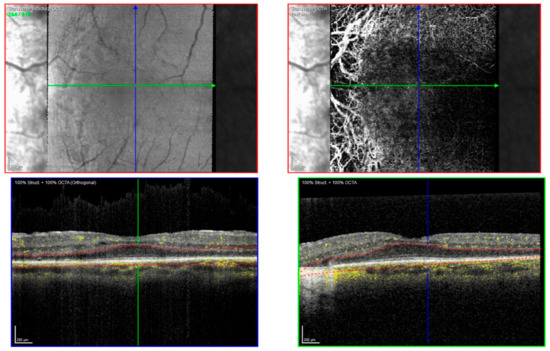

| OCT | No deposits, absence of RPE and photoreceptors in affected areas | Subretinal deposits, irregular photoreceptor loss |